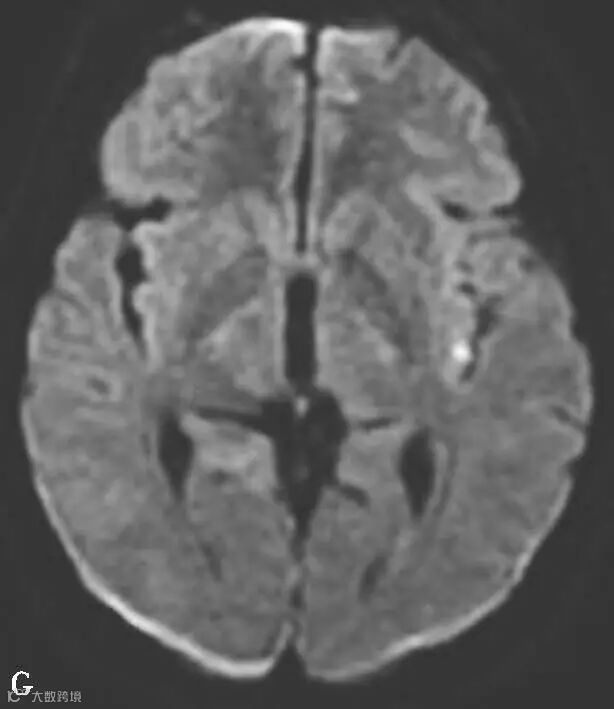

图6-11-2 弥漫性轴索损伤

男,36岁,外伤后2天。A~J(A、B.T2WI,C、D.T1WI,E、F.T2WI-FLAIR,G、H.DWI,I、J.ADC图):双侧额叶、半卵圆中心及胼胝体压部可见多发斑点状等T1稍长T2信号,边缘不清,FLAIR及DWI呈高信号,ADC图病灶信号减低 。